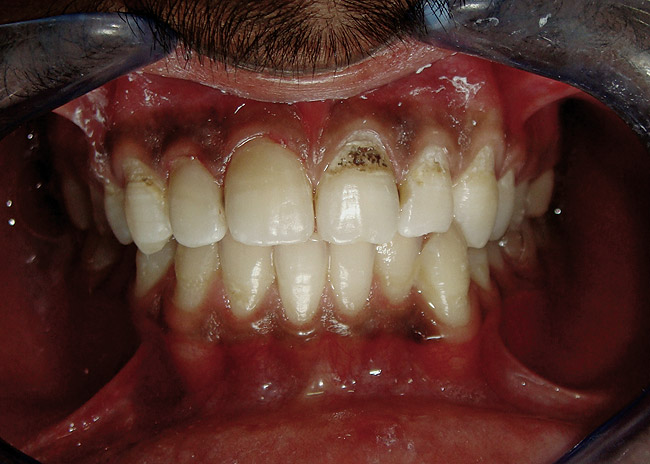

Figure 4  Final composite restorations with respect to upper right incisors.

Figure 4